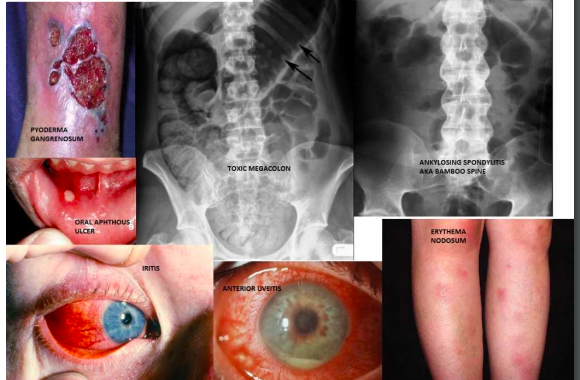

Which skin manifestation is a common finding in those w/ IBD?

What are 4 potential serious complications of a patient w/ UC?

What are 5 potential complications or risks for someone with Chron Disease?